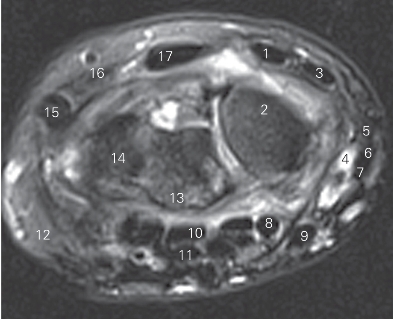

图4-42 经近侧列腕骨近侧份的横断层MR T2WI FS

1 桡侧腕短伸肌腱 tendon of extensor carpi radialis brevis

2 舟骨scaphoid bone

3 桡侧腕长伸肌腱 tendon of extensor carpi radialis longus

4 桡动脉radial artery

5 拇长伸肌腱 tendon of extensor pollicis longus

6 拇短伸肌腱 tendon of extensor pollicis brevis

7 拇长展肌腱 tendon of abductor pollicis longus

8 拇长屈肌腱 tendon of flexor pollicis longus

9 桡侧腕屈肌腱 tendon of flexor carpi radialis

10 指深屈肌腱 tendon of flexor digitorum profundus

11 指浅屈肌腱 tendon of flexor digitorum superficialis

12 小鱼际hypothenar 13 月骨lunate bone

14 三角骨triquetral bone

15 尺侧腕伸肌腱 tendon of extensor carpi ulnaris

16 小指伸肌腱 tendon of extensor digiti minimi

17 指伸肌腱 tendon of extensor digitorum